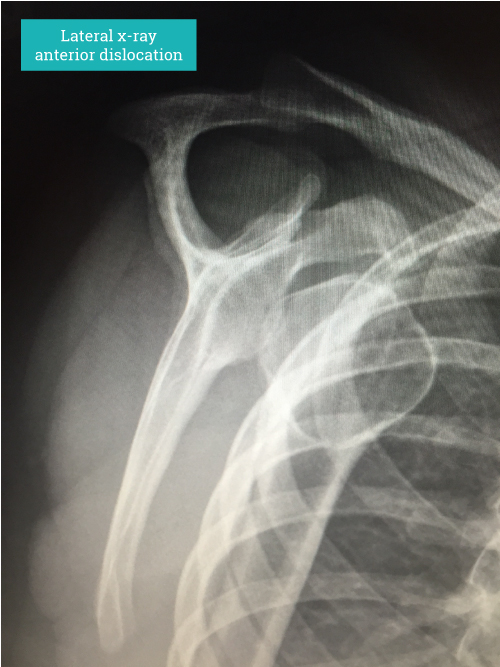

Diagnosis is based on clinical history and signs. Confirmation by an x-ray showing the dislocated shoulder can be helpful. Imaging such as MRI scanning will show the underlying structural problems such as a labral tear (soft tissue Bankart lesion), bony injuries such as glenoid rim fractures (bony Bankart lesion) and impaction fractures on the back of the humeral head (HillSachs lesion) where It has contacted the anterior glenoid during the dislocation. In older persons the risk of damaging the rotator cuff at the time of dislocation is increased and should be actively looked for as rotator cuff tears in these circumstances can be quite substantial.

“Diagnosis is based on clinical history and signs. Confirmation by an x-ray showing the dislocated shoulder can be helpful.”